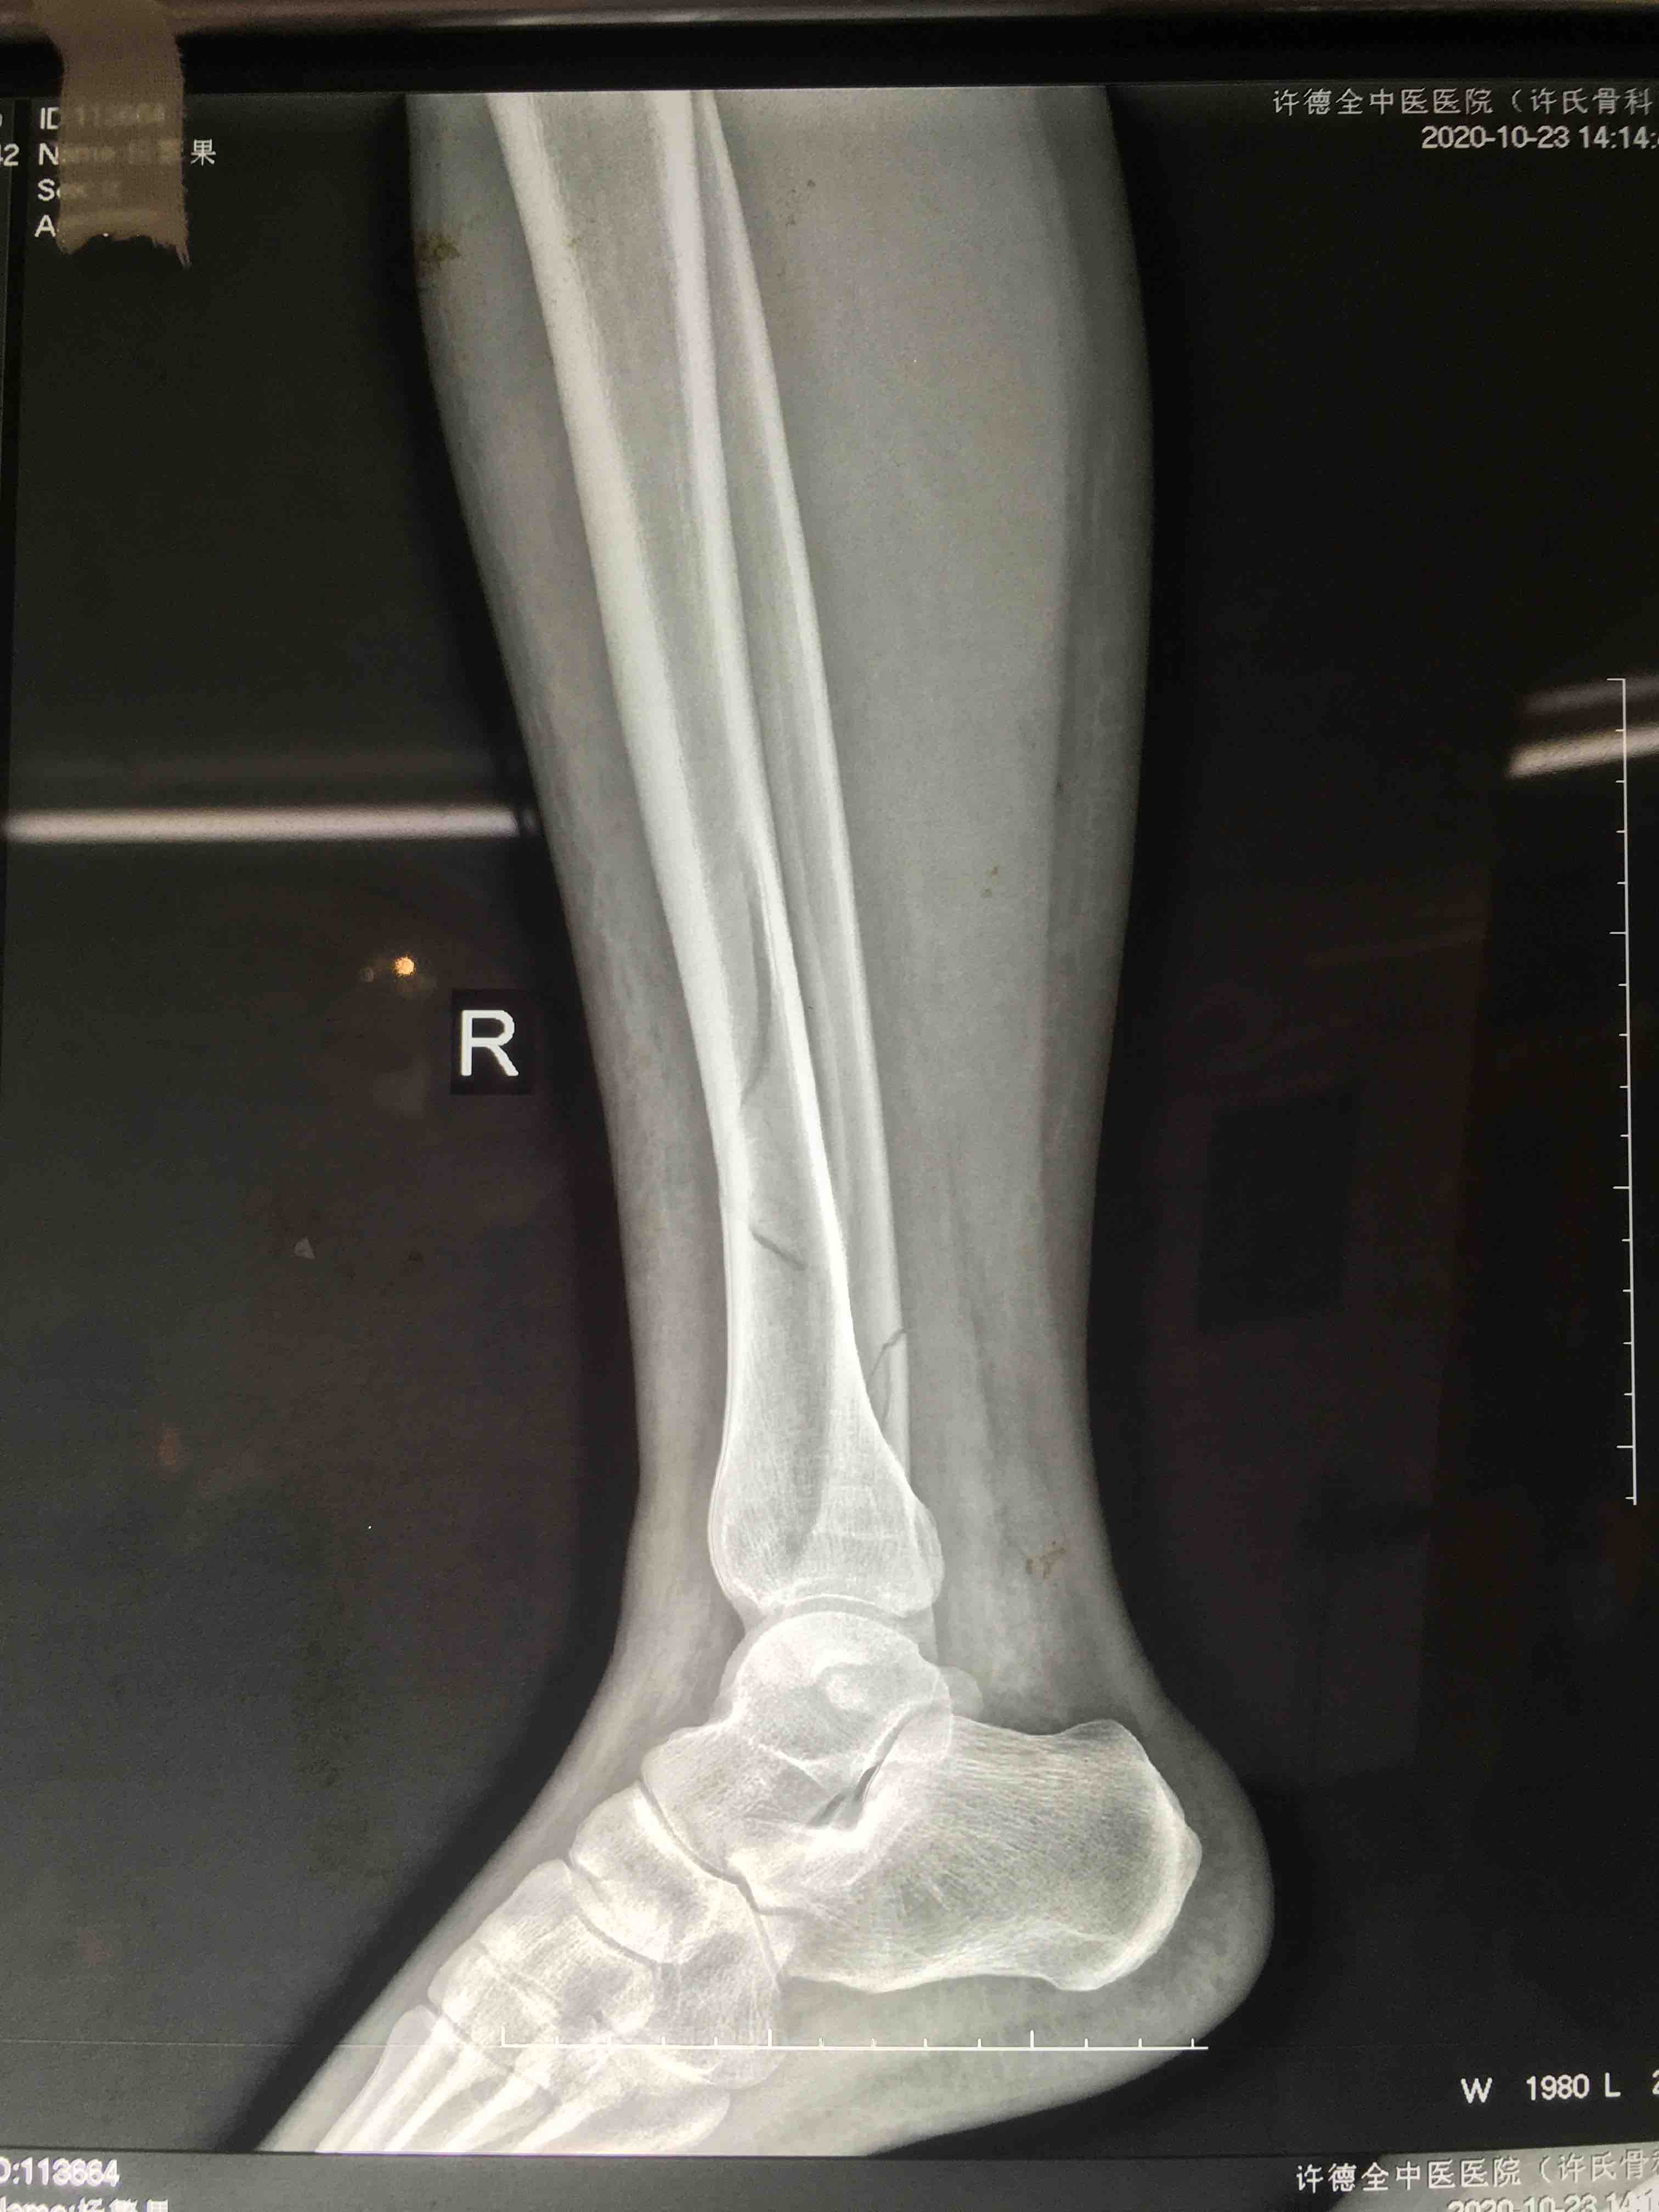

胫腓骨下段骨折(微创固定)

摔伤后右小腿肿痛,活动受限1小时入院。既往身体健康,无特殊不良嗜好。

生命体征平稳,心肺复未见明显异常。右小腿肿胀,局部皮色皮温正常,压痛及叩痛阳性,可及骨擦音,活动受限,末梢血运感觉正常。

在腰麻下行切复内固定术,术后抗炎,消肿对症治疗。